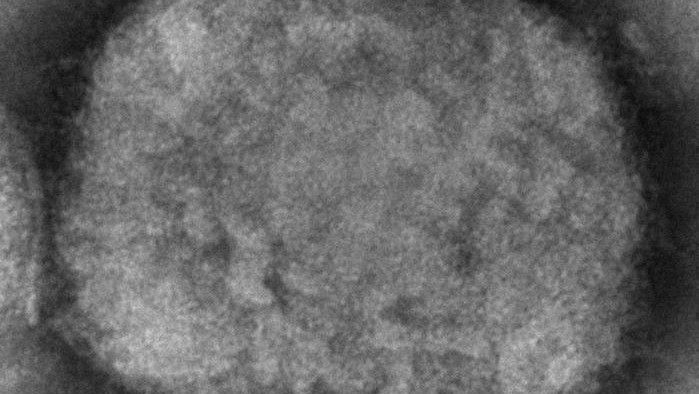

SANTA ANA, Calif. (CNS) — Orange County health officials Wednesday confirmed the county's first case of monkeypox in a person under age 18.

No details about the case or the patient were released. Health officials said only that they are working to identify close contacts of the patient and offer vaccines to those who may have been exposed.

"Please remember that monkeypox is very uncommon in children," Dr. Regina Chinsio-Kwong, county health officer, said in a statement. "It is important to note that many childhood illnesses can cause rashes. If you or your children have a new or unusual rash, please follow preventive guidance and seek medical attention from a qualified health care professional for further recommendations."

Orange County has identified a total of 126 monkeypox cases, most of them in gay men.

Health officials urged people showing symptoms of the illness to contact their health care provider, cover the rash area with clothing, wear a mask, avoid close or skin-to-skin contact with others and isolate away from family members and pets.